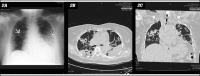

Lemierre's syndrome is characterized by an oropharyngeal infection with internal jugular vein thrombosis followed by metastatic infections in other organs. This infection is usually caused by Fusobacterium spp. In this report, we present a rare case of Klebsiella pneumoniae-associated Lemierre's syndrome in a patient with poorly-controlled diabetes mellitus. The infection was complicated by septic emboli in many organs, which led to the patient's death, despite combined antibiotics, anticoagulant therapy, and surgical intervention. Therein, a literature review was performed for reported cases of Lemierre's syndrome caused by Klebsiella pneumoniae and the results are summarized here.